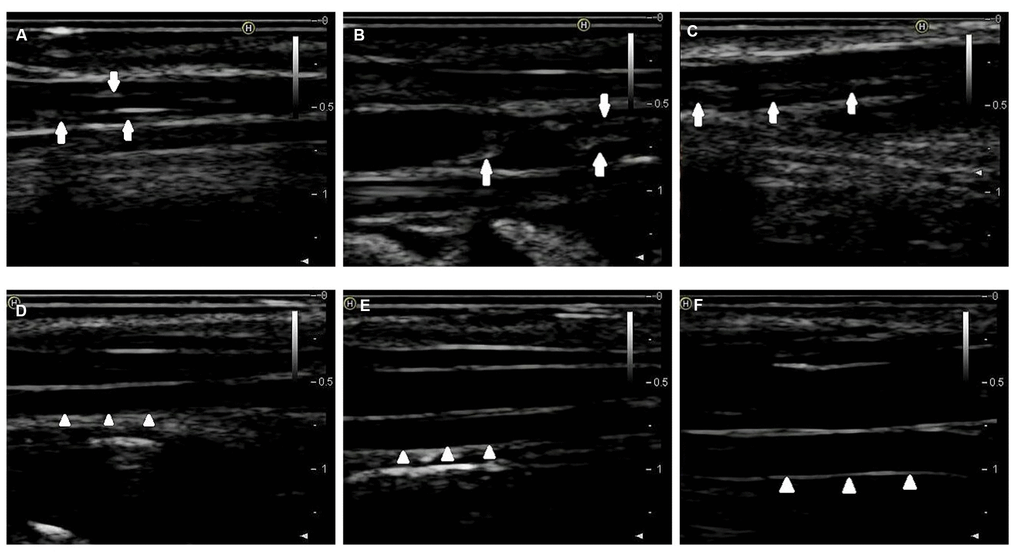

By combining endothelial injury and an atherogenic diet, we thickened and roughened the intima and induced multiple irregular hypoechoic plaques in rabbit right common carotid arteries as indicated by two-dimensional (2D) ultrasound at the 12th week (Figure 1A–1C). In contrast, the carotid artery intima of rabbits fed normal chow remained clear, smooth and continuous with no obvious changes (Figure 1D–1F). Hematoxylin and eosin (H&E) was used to stain vascular tissue from sites with obvious plaques in the AS group, and tissues were imaged using 2D ultrasound. Thickened intimae, foam cell deposition, smooth muscle cell proliferation and varying degrees of plaques on rabbit carotid artery intimae were observed (Figure 2A–2C). However, the intimae of the control group were smooth and intact, and no obvious foam cell deposition or smooth muscle cell proliferation was observed (Figure 2D–2F).

Figure 1. 2D-ultrasound images of rabbit carotid arteries at the 12th week. (A–C) 2D-ultrasound images reveal that obvious atherosclerotic plaques formed on rabbit carotid arterial intima as the arrows show. (D–F) 2D-ultrasound images demonstrate that carotid arteries intima of rabbits treated with normal chow still maintain smoothness as the arrows show.